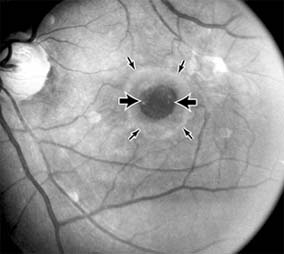

Nonexudative age-related macular degeneration is characterized by variable degrees of atrophy and degeneration of the outer retina, retinal pigment epithelium, Bruch's membrane and choriocapillaris. Of the ophthalmoscopically visible changes in the retinal pigment epithelium and Bruch's membrane, drusen are the most typical (Figure 10-1). Drusen are discrete, round, yellow-white deposits of variable size beneath the pigment epithelium and are scattered throughout the macula and posterior pole. With time, they may enlarge, coalesce, calcify, and increase in number. Histopathologically, most drusen consist of focal collections of eosinophilic material lying between the pigment epithelium and Bruch's membrane; they therefore represent focal detachment of the pigment epithelium. In addition to drusen, clumps of pigment irregularly dispersed within depigmented areas of atrophy may progressively appear throughout the macula. The level of associated visual impairment is variable and may be minimal. Fluorescein angiography demonstrates irregular patterns of retinal pigment epithelial hyperplasia and atrophy. Electrophysiologic testing in most patients is normal.

Figure 10-1

Figure 10-1: Age-related macular degeneration with discrete (small arrow) and large confluent (large arrow) macular drusen.